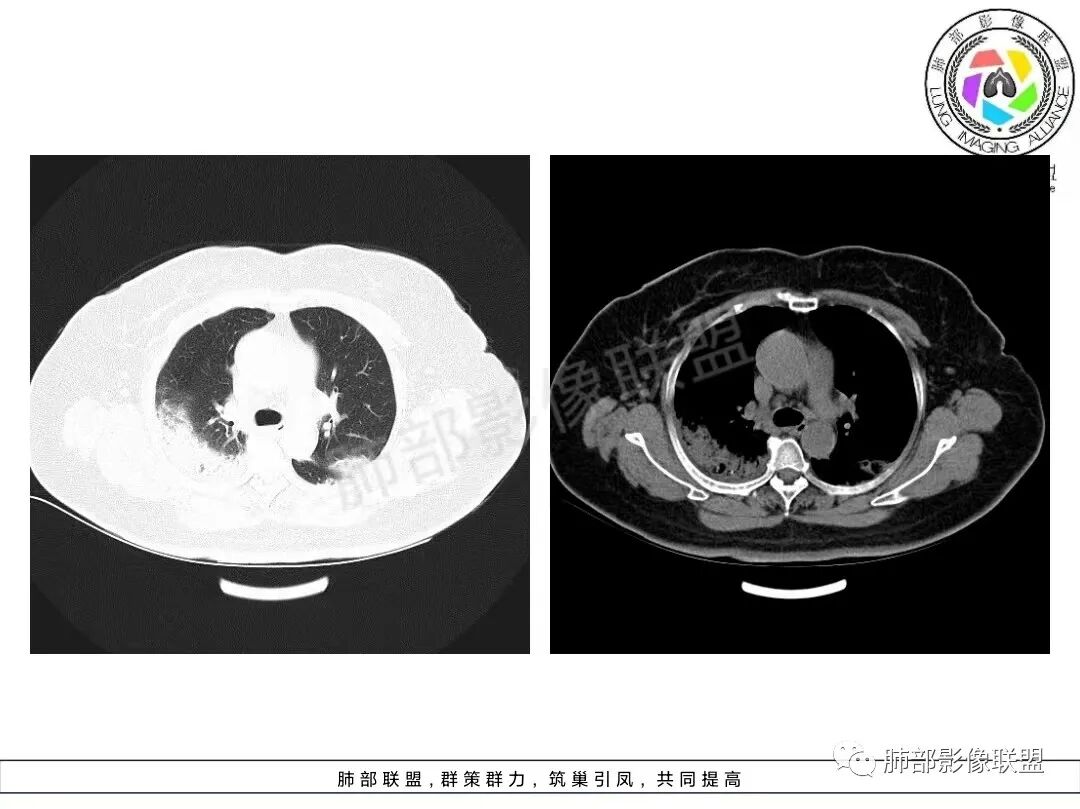

老年女性,咳嗽、咳黄白痰,无发热,化验炎性指标高,右肺胸膜下实变,其内支气管充气、扩张,周围索条,左肺胸膜下多发结节及斑片实变,胸膜下线影,右侧少量胸水,考虑机化性肺炎,鉴别隐球菌、粘液腺癌

双肺胸膜下多发斑片及大片实变影,边缘清晰,长轴平行于胸膜,部分病灶呈细网格状,右侧胸膜增厚,右侧叶间胸膜增厚,血糖高,感染指标高,考虑OP,鉴别隐球菌

老年女性,咳嗽、咳黄白痰,无发热,右肺胸膜下实变,其内支气管充气、扩张,周围索条,左肺胸膜下多发结节及斑片实变,胸膜下线影,右侧少量胸水,考虑机化性肺炎。

2、影像特点:双肺胸膜下为主、多发斑片影、结节样实变影及磨玻璃样密度影,大部分病灶边缘平直、边界清,磨玻璃密度病灶内可见细网格影,部分病灶内可见支气管扩张表现,部分支气管直达远端,部分中断于病灶中部。部分病灶有侧向融合趋势。